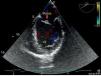

Os tumores cardíacos primários são raros em todas as faixas etárias, com uma prevalência reportada entre 0,0017‐0,003%. Os autores apresentam o caso de um homem, 37 anos de idade, sem antecedentes patológicos relevantes, que recorreu ao serviço de urgência por quadro clínico de instalação súbita de hemiparesia direita. O estudo complementar revelou pequena área hipodensa no putamen esquerdo, sendo diagnosticado AVC isquémico, pelo que foi internado na unidade de AVC. Durante o estudo etiológico do evento cerebrovascular em idade jovem, fez ecocardiograma transtorácico (ETT) que demonstrou massa aderente ao folheto anterior da válvula mitral (Figura 1). Nesse contexto fez ecocardiograma transesofágico (ETE) para melhor esclarecimento do quadro que revelou pequena massa ecodensa de 0,5cm2, pediculada, de bordos bem definidos aderente ao folheto anterior da válvula mitral na face auricular, sugestiva de fibroelastoma papilar mitral (Figuras 2 e 3). Esta massa não condicionava insuficiência mitral (Figura 4) e o restante exame ecocardiogáfico demonstrou uma fração de ejeção do ventrículo esquerdo estimada em 65%, sem outras valvulopatias. Posteriormente o doente foi reencaminhado para o Centro de Cirurgia Cardiotorácica para excisão de massa, cujo exame macroscópico demonstrou formação nodular de 0,6cm de superfície espiculada e esbranquiçada, de consistência mole‐elástica. O exame histopatológico revelou mixoma cardíaco. Os autores apresentam este caso pela particularidade da apresentação, nomeadamente as caraterísticas ecocardiográficas.

Ecocardiograma transesofágico em corte longitudinal onde se visualiza massa ecodensa, pediculada, aderente ao folheto anterior da válvula mitral na face auricular. Visualiza‐se também o apêndice auricular esquerdo sem evidência de trombo.